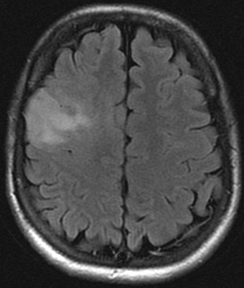

Trois ou quatre ?

Dr Nadine Martin-Duverneuil Pitié-Salpêtrière - Paris

Clinique :

Femme de 40 ans, sans antécédent, parésie progressive de la main gauche.

Imagerie IRM conventionnelle :

Lésion frontale droite cortico-sous-corticale, relativement bien limitée, en hypersignal FLAIR.

Absence d’œdème périlésionnel.

Effet de masse visible sur les sillons et la voûte avoisinants.

La masse est nettement hypointense en T1. Après injection de gadolinium, prise de contraste significative, hétérogène, à prédominance superficielle et à extension cortico-méningée.

Quel est votre diagnostic ?